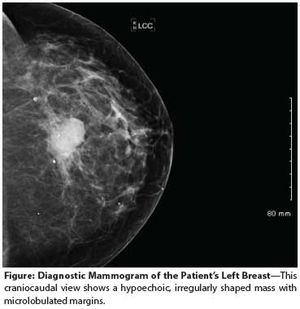

The patient presented to her primary care physician 3 months prior with an inverted left nipple and a palpable lump that was highly suggestive of neoplasm on mammogram. An ultrasound-guided core biopsy revealed an infiltrating solid-type ductal carcinoma in situ. The estimated size of the mass was approximately 1 cm. She had no symptoms suggestive of metastatic disease.